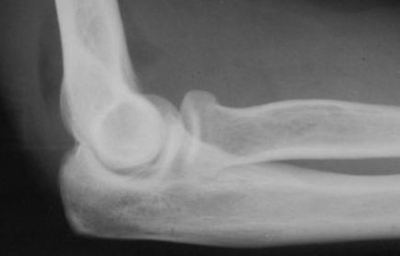

4 / 10

4. Paciente chega no seu consultório com dores agudas no cotovelo após queda com a mão estendida. Tirou uma radiografia, cujo laudo foi negativo. Em relação a esta imagem, qual das alternativas abaixo está INCORRETA?